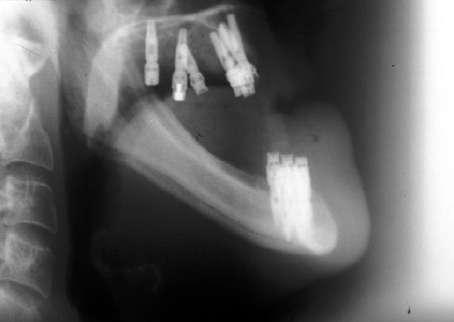

La cirugía ortognática se realiza bimaxilar, procediéndose al avance del maxilar superior y la retrusión de la mandíbula. En las imágenes intraquirúrgicas vemos el gran avance realizado en el maxilar superior y la distancia que se pretende reducir en la mandíbula mediante una osteotomía sagital deslizándose las corticales una sobre otra para conservar intacto el canal del nervio dentario (figuras 9-12).

Figuras 10 y 11. Inicio de la osteotomía mandibular y finalización de la misma con la colocación de la mini-placa de fijación y relleno del gap con hueso autólogo particulado (triturado del fragmento óseo retirado) unido al PRGF-Endoret.

Figura 12. Radiografía panorámica con la cirugía bimaxilar terminada y las prótesis sobre implantes en oclusión.

Figuras 13-16. Imágenes de retirada de las miniplacas de la mandíbula donde podemos observar la regeneración ósea completa de la zona donde se produjo la osteotomía sagital.

Figura 26. Radiografía a los 23 años de seguimiento con los implantes sin pérdidas óseas significativas. La prótesis inferior ha sido sustituida por otra con diferente estructura pero la estabilidad de los implantes y del tratamiento se mantiene a largo plazo.